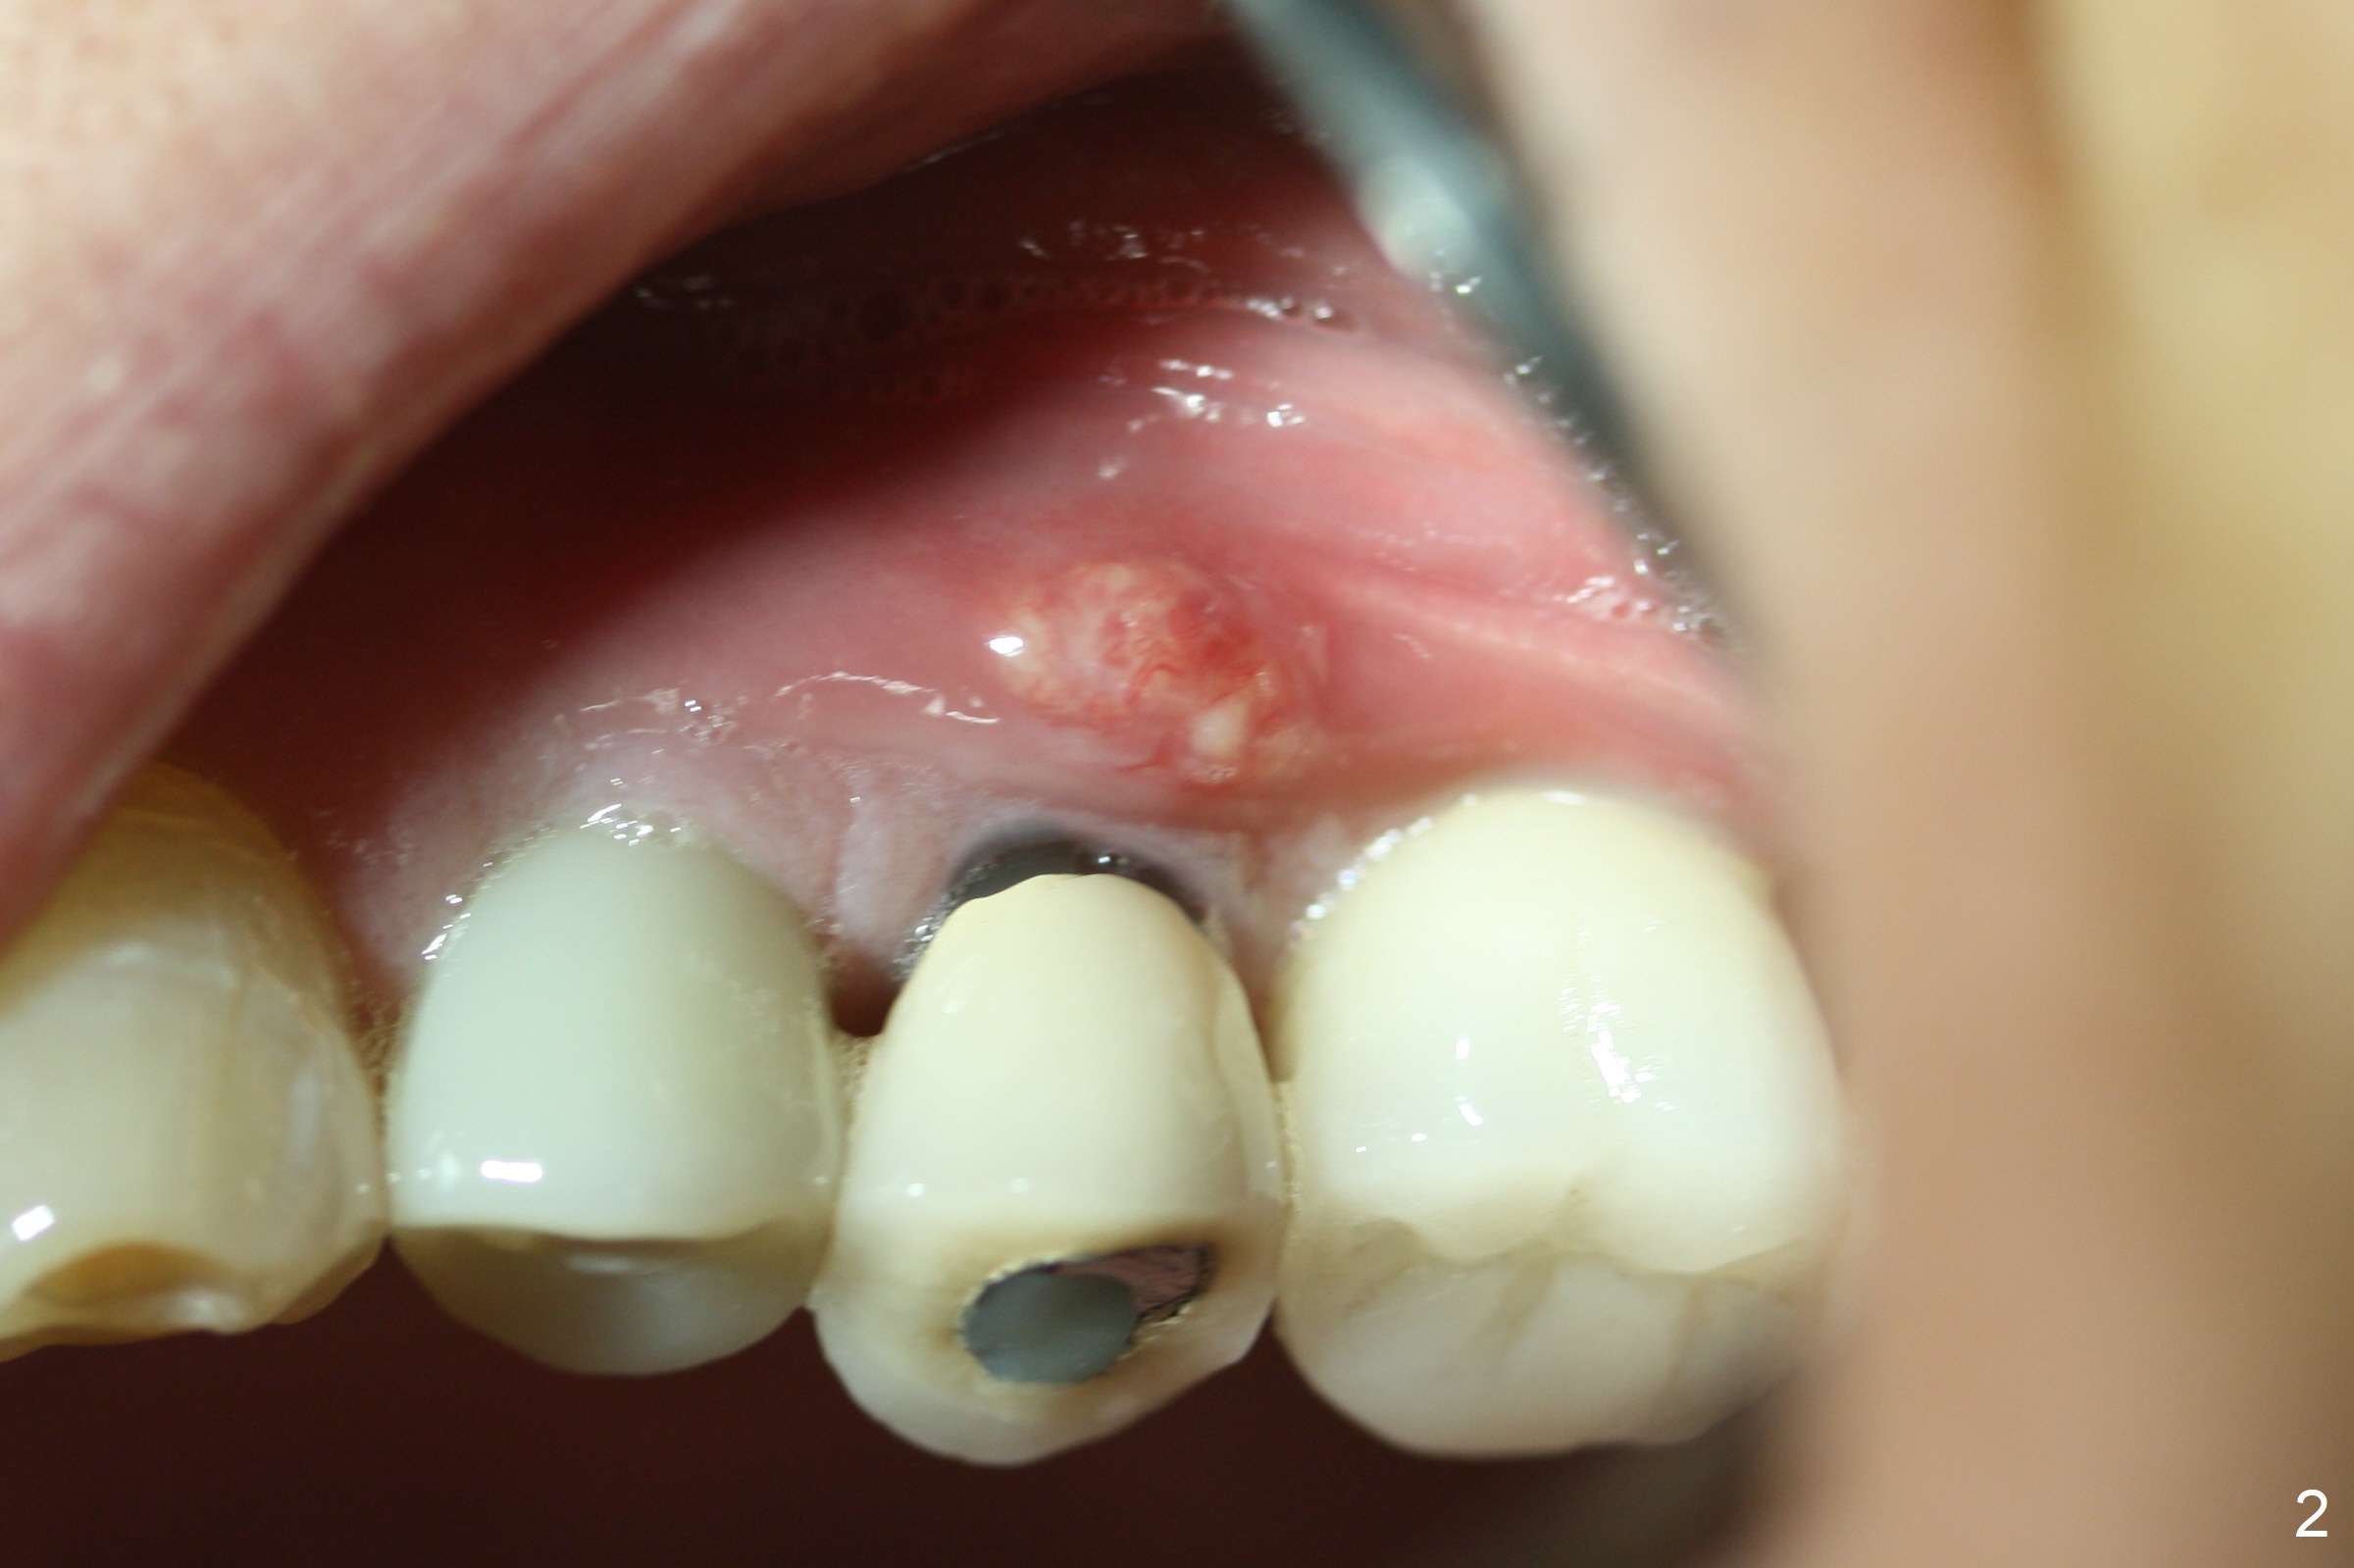

A 75-year-old man has bite pain at #13 after RCT (root resorption, Fig.1). The tooth appears to be non-salvageable (Fig.2). There seems to be sufficient bone for the longest tissue-level implant (Fig.3,4). Take preop PA and intraop one as soon as a 2 mm drill is used for trajectory confirmation.